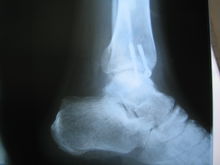

踝骨骨折

踝骨骨折會局部腫脹,壓痛和功能障礙。診斷時,首先應根據外傷史和臨床症狀以及X 線片顯示的骨折類型,分析造成損傷的機制。創傷性關節炎。